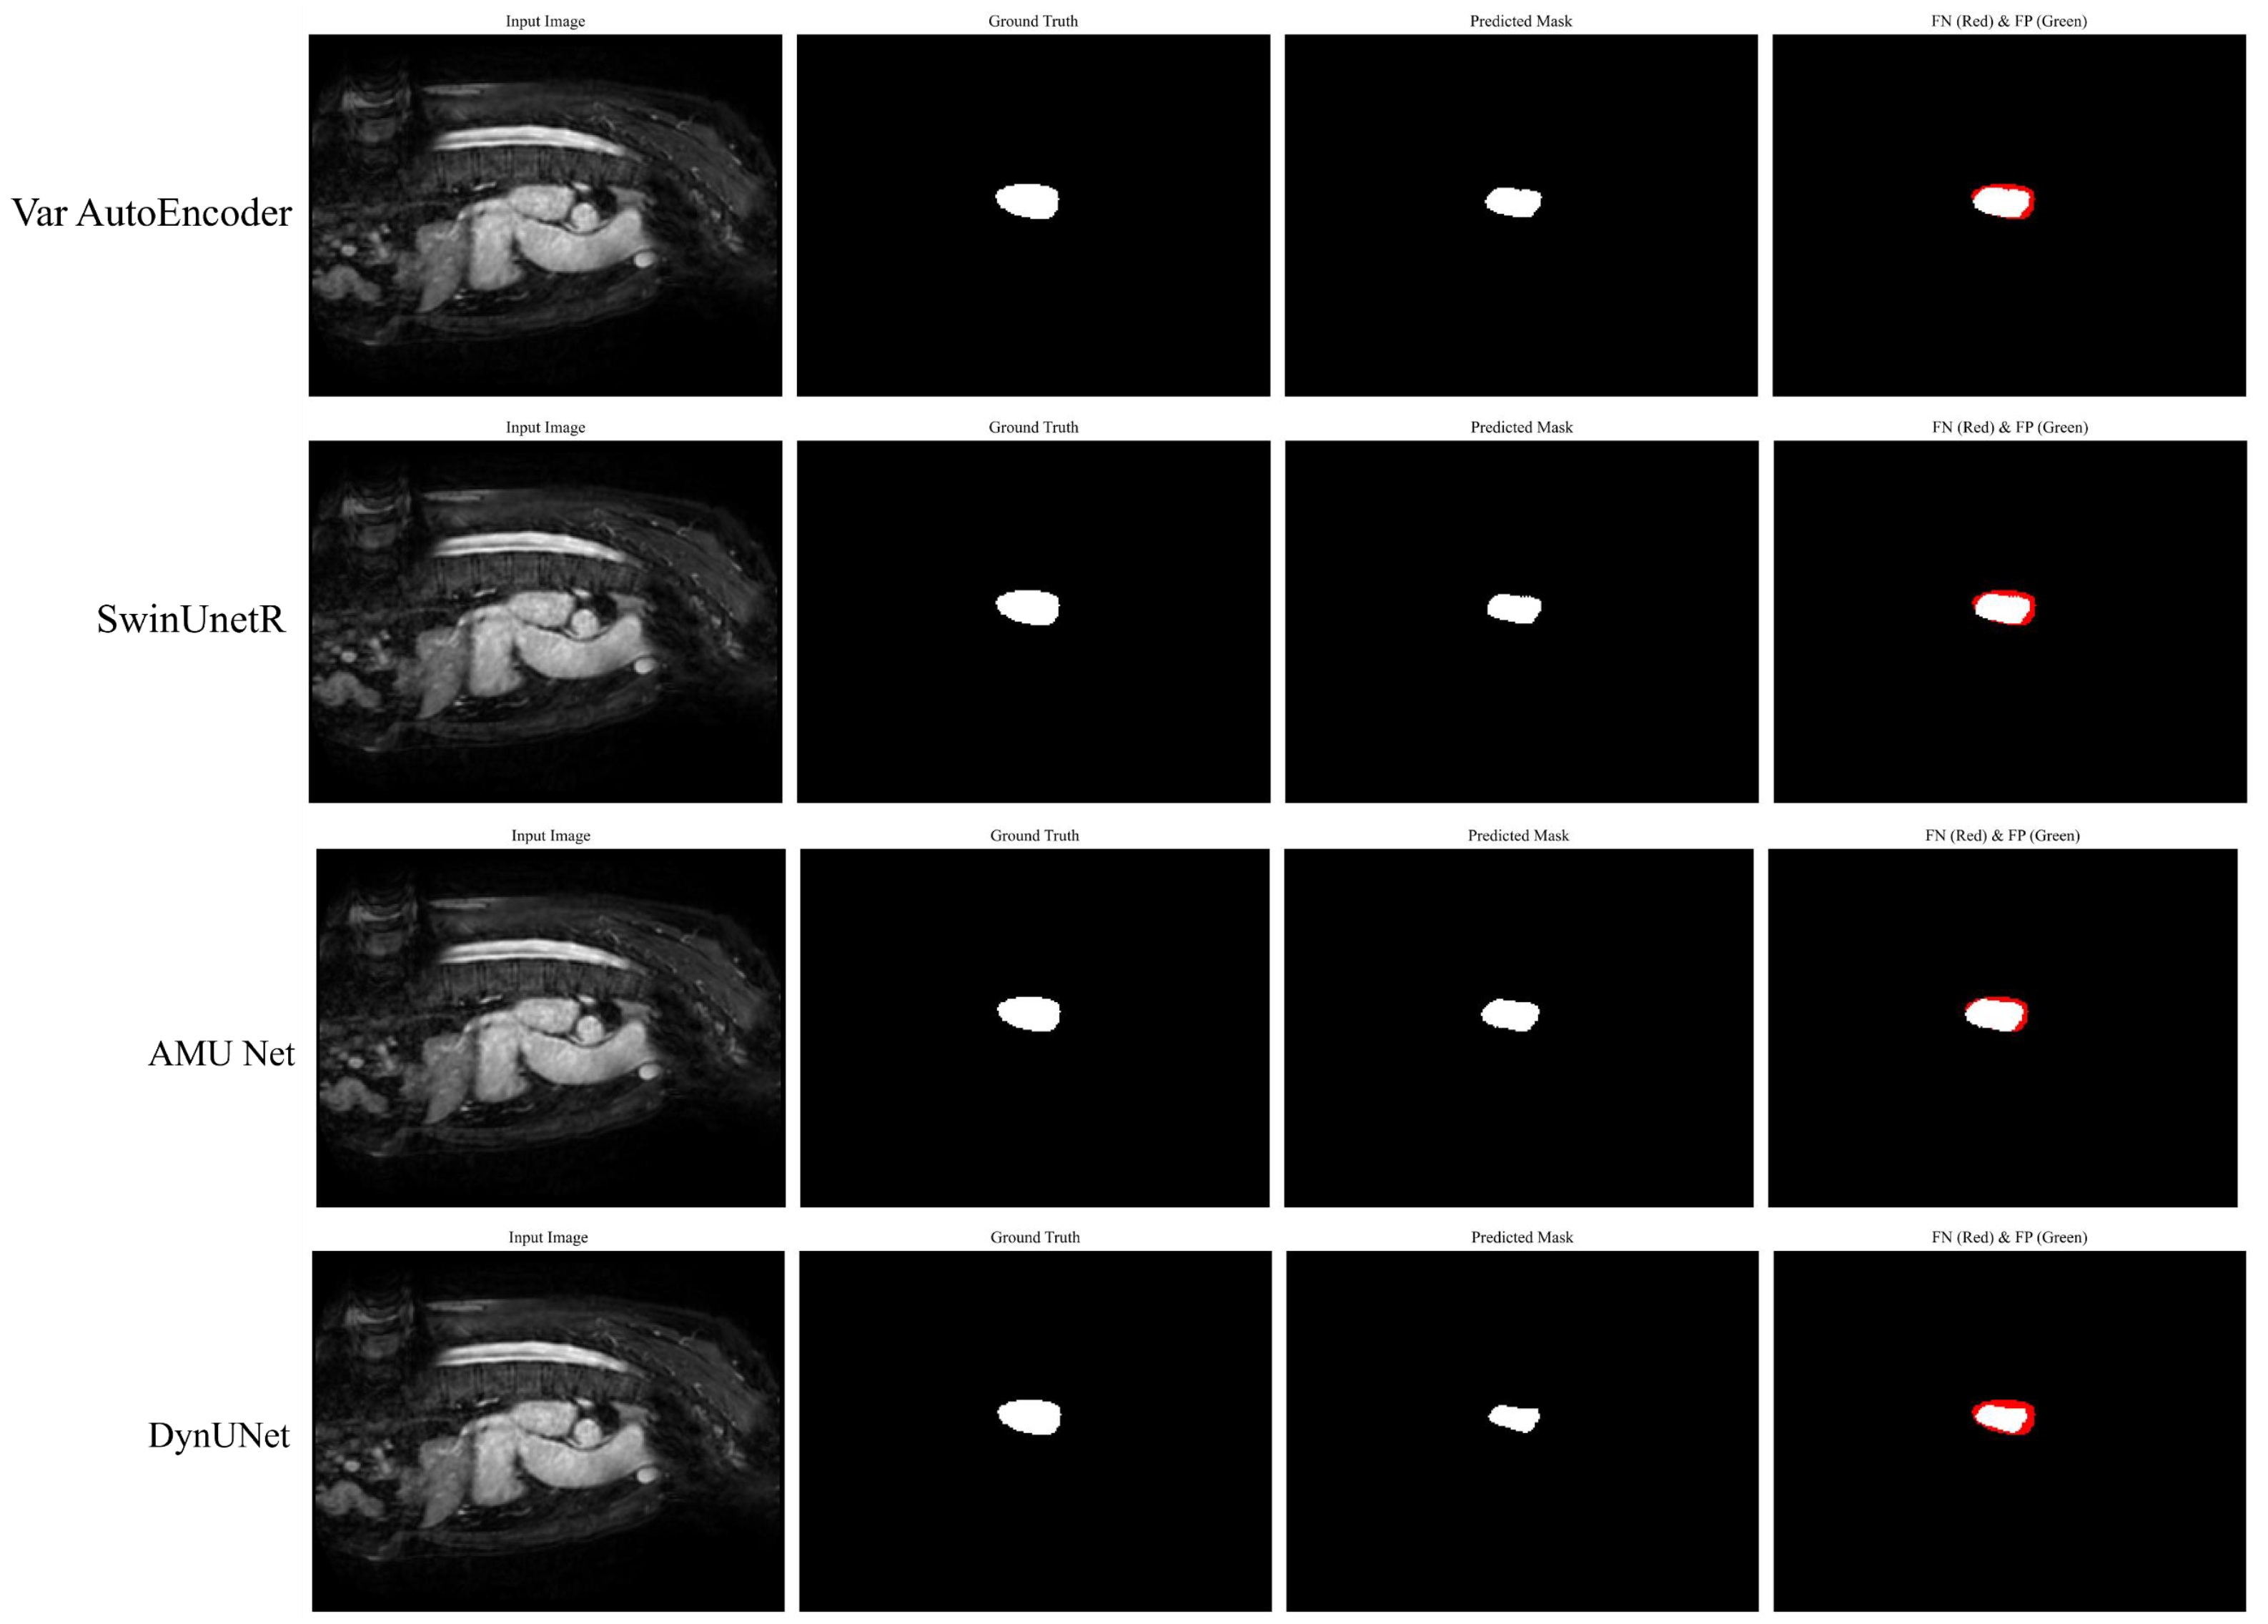

Figure 9 provides a detailed visual analysis of the segmentation performance through the visualization of corresponding false positives (FPs) and false negatives (FNs) on challenging images. The false negatives are highlighted in red, while false positives are marked in green. Across the samples, the predicted masks show a strong resemblance to the ground truth, which reflects the model’s high accuracy in capturing the target regions. However, we also observed some errors at the boundaries, which reveals areas where the model missed true positives. These errors predominantly occur along the edges, which indicates the challenges in precise boundary delineation on challenging images. Nonetheless, the relatively small extent of FNs and FPs compared to the overall segmentation highlights the robustness of the model.

Figure 9.

The visualization results FPs and FNs on challenging images.

Figure 10 shows the visual comparison of segmentation results produced by our proposed AMU-Net model and four other top-performing models. The columns represent the input images, ground truth masks, predicted masks, and FN -FP areas. Our AMU-Net demonstrates superior segmentation performance which is closely aligned with the ground truth. It also shows lower FN and FP regions compared to the other models such as Var AutoEncoder, SwinUnetR, and DynUNet. This comparison highlights the effectiveness of our AMU-Net in accurately segmenting the target regions compared to other models.

Figure 10.

The visualization results of different models along with FP and FN.